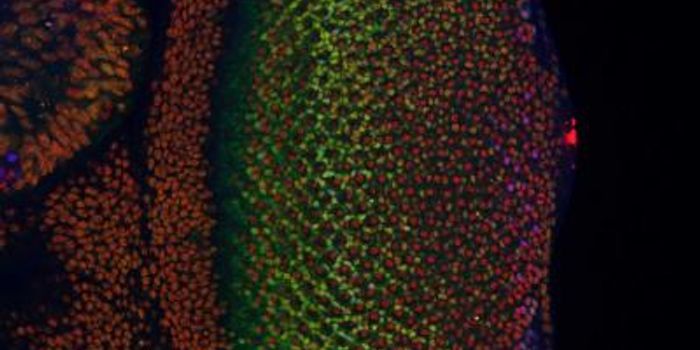

FEB 21, 2023Cell & Molecular BiologyThe Griffith Lab at UNC discovered telomeric protein & potential biomarker VR (green), shown in the nuclei (blue) of hum ...